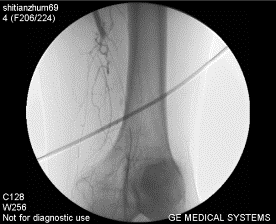

3、動脈造影和數字減影血管造影:是最精確的檢查方法,也是目前診斷血管疾病的重要手段之一。它對於診斷動脈閉塞性疾病有著重要的價值。動脈造影不僅能清楚顯示動脈的形態,明確動脈阻塞的部位,也能詳細地了解阻塞部位遠端血管以及側支循環建立的情況,有助於確定外科治療方案及估計手術預後。然而,這畢竟是一種介入性檢查方法,尤其是造影劑可能對腎功能不全的患者套用受限。因此,該方法多用於需要手術或經皮介入治療的病人。目前動脈造影技術主要套用於血管外科手術前後,除套用於診斷血管疾病外,還可以藉助造影法進行狹窄血管的擴張、血管栓塞、血管內支架等血管介入性治療等。

動脈硬化閉塞症--影像6、血管造影:血管造影一直被作為ASO診斷的“金標準”,經腰部腹主動脈穿刺或經股動脈穿刺插管造影術可以提示動脈病灶的確切範圍、是否為多發性以及動脈阻塞程度,也可了解側支循環建立的情況,是制定手術方案所不可缺少的檢查方法。